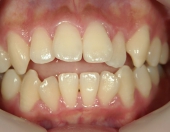

主訴:奥歯で噛んだときに前歯が噛み合わない

━━ 当院で働いている池谷彩乃さんが、前突および開咬を舌側ワイヤー矯正で治療しました。

中学生になり第二大臼歯が生えてから、真ん中の前歯2本が出てきて、八重歯も目立つようになりました。はじめは八重歯がチャームポイントだと捉えて気にしていませんでしたが、年々歯並びが悪化している気がしました。そのうち前突が原因で口が閉じづらく、寝ている時は口呼吸になってしまいました。

高校時代には、歯並びを改善しようと様々な矯正サイトを閲覧し、自分自身が開咬であることを知りました。開咬とは、上下の歯を噛み合わせた時に前歯に隙間ができることを言います。そういえば、麺を前歯で噛みきること、ハンバーガーにガブッと噛みつくことができませんでした。

2年を少し過ぎたころには歯並びが良くなり、開咬もだいぶ改善されました。結婚式を予定していたため早期終了をさせていただきましたが、開咬が治ってハンバーガーをガブッと噛みきることができるようになって、とっても嬉しいです。式でもきれいな歯並びで、思いっきり笑うことができました。